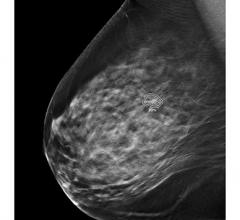

Breast Imaging

Women's health related to breast imaging, including mammography, breast MRI, ABUS, automated breast ultrasound, breast ultrasound, breast biopsy, PEM and positron emission mammography.

Despite decades of progress in breast imaging, one challenge continues to test even the most skilled radiologists ...

Breast cancer remains a significant health concern, responsible for more than 600,000 deaths annually. Early detection ...